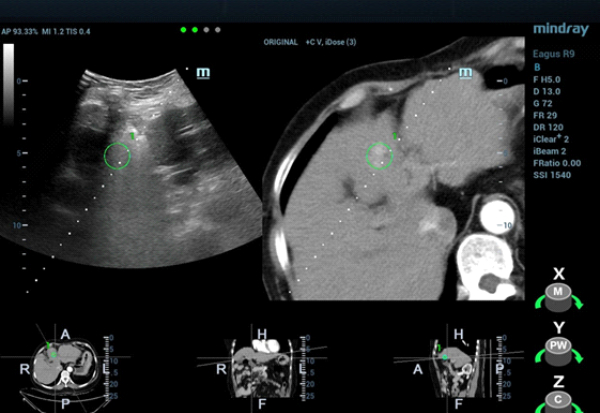

CT??? ??? S4?? ??? ??? ?? ???????? ??? ?????. CEUS(Contrast-Enhanced Ultra Sound)????? ?????? ??? ??? ??? ??? ???? ? ??? ???? ???? ??? ???????.

??? ??? ?? ????? ???(MWA)? ?? ?????? ?? ?????? ??? ???? ??? ?? Contrast-enhanced CT? ???? ??? ?? ??? ??? ?? ??? ?? ??? ????? ???? ???? ????? ??(MWA)? ??? ???????.

??? ????? ??? 2D ??? ??? ???? ???? ???? ??? ? ????? ??? ??? ?? ?????? ???? ?? ??? ???? ???? ??? ? ?????. ??? ??? ???? ??? ?? CT ??? ??? ???? ??? ??? ??? ?? MWA? ?? ???? ??? ???? ?????. CEUS(Contrast-Enhanced Ultra Sound)? ???? ?? ? ??? ??? ????, ?? ? ?? ??? ???? ?? ?? ??? ???????.?

?? ??? ??? CEUS(Contrast-Enhanced Ultra Sound)? ???? ????? ??? ??? ??? ???? ??? ? ??, ????? ???? ???? ????, ?? ??? ?????? ??? ? ????. ??? ??? ??? ???? ??? ?? ????? ??(Ultrasound-guided MWA)? ???? ?? ??? ?????.